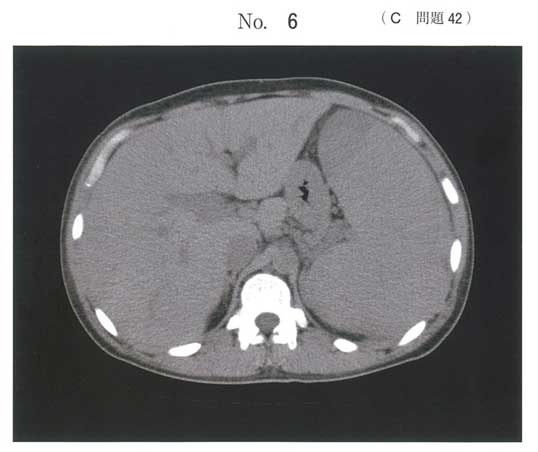

脾腫

CMPDは明らか。脾腫がありCMLの可能性が高いが、骨髄穿刺と併せてph1の有無見る必要性あり。aかな。ph1陰性であればJACK1,CALRを見てね